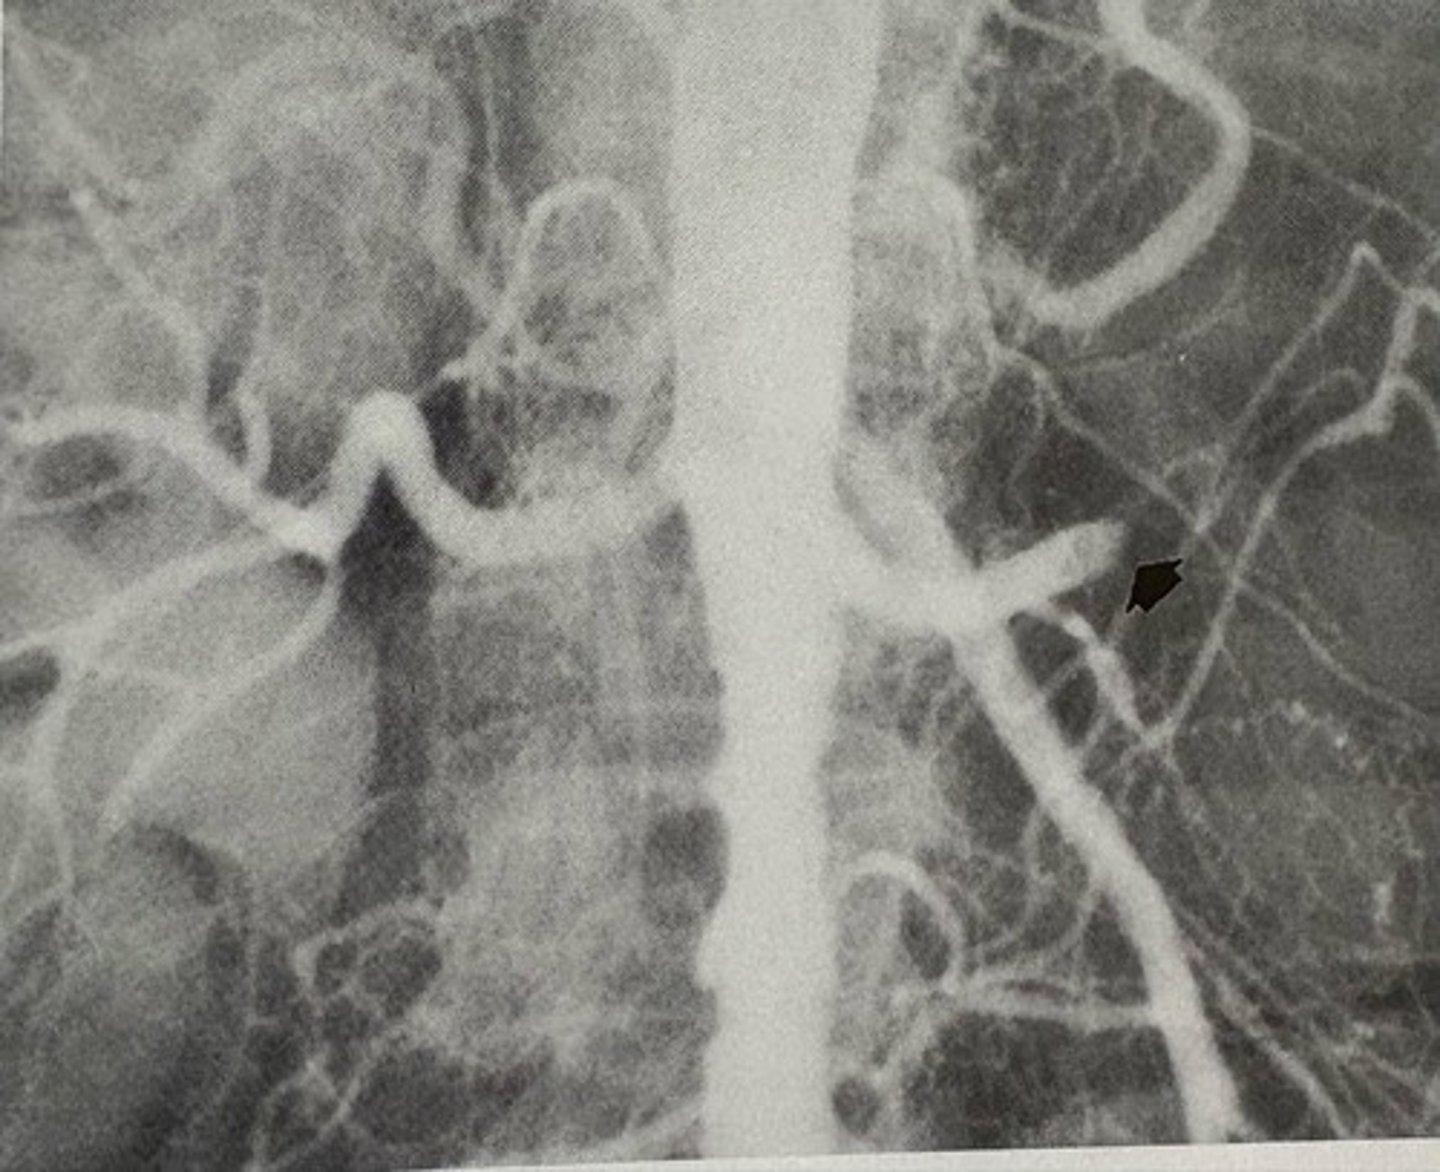

acute embolism occlusion of the left renal artery

what pathology is present?